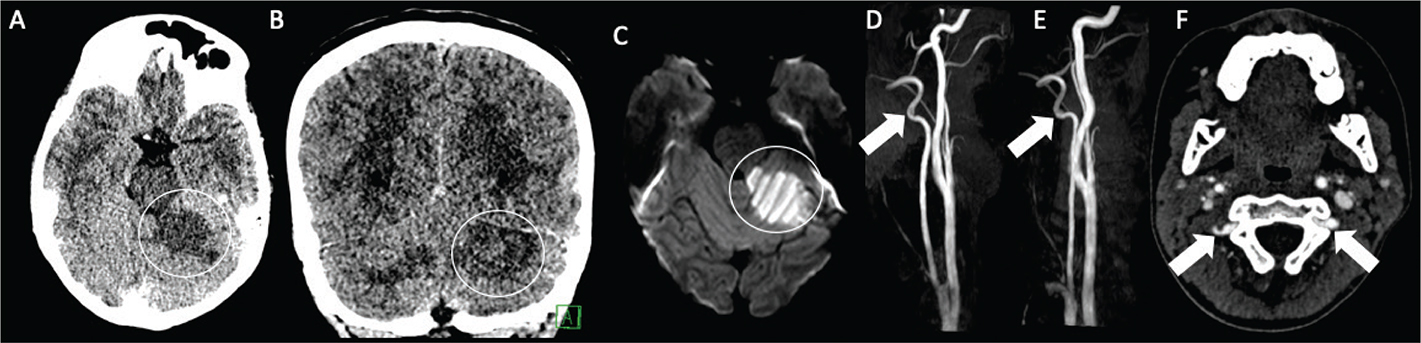

Venous sinus thrombosis and venous infarct

Venous thrombosis is a common cause of spontaneous cerebral hemorrhage, both intraparenchymal and, rarely, epidural, with nearly 70% of pediatric venous infarcts becoming hemorrhagic (Figure 8) (104, 105). Parasagittal injuries are seen with superior sagittal sinus thrombosis, temporal lobe hematomas with transverse sinus thrombosis, and thalamic hemorrhage with vein of Galen/straight sinus thrombosis.

Fig 8

Figure 8. An 18-year-old male who presented with intractable headache found to have left vein of Labbe thrombosis and hemorrhagic venous infarct. DWI (A) and associated ADC (B) demonstrates associated vasogenic and cytotoxic edema. Noncontract T1-weighted image (C) shows high signal within the left vein of Labbe (white arrowhead) with associated filling defect on contrast enhanced study (white arrow) (D). No underlying vascular malformation or mass was identified. T2-weighted MRI (E) demonstrates a left posterior temporal hematoma with associated edema. Noncontrast axial CT image (F) demonstrates parenchymal hemorrhage with hyperdensity within the vein of Labbe (black arrow).

In infants and children, MRI is the imaging modality of choice. Routine T1- and T2-weighted images should be obtained (and FLAIR in older infants and in children), in addition to DWI, GRE or SWI images, and MRV. Acute (<7 days old) thrombus exhibits low signal intensity due to the presence of deoxygenated hemoglobin beginning quickly following its development, often with apparent expansion of the affected sinus on GRE and reduced diffusivity (106). If the thrombosis is subacute (between 6 and 15 days), T1-weighted images show high signal intensity of the clot, potentially with persistently reduced diffusion during the intracellular stages of hemoglobin breakdown (107).

CT venography, showing thrombi as hypodense areas within the affected venous structure (“empty delta sign” with thrombosis of the superior sagittal sinus or other veins captured in cross section), is very sensitive and specific for the diagnosis of dural sinus thrombosis, but of limited diagnostic value for diagnosing cortical vein thrombosis and often avoided due to the utilization ionizing radiation (108). Multiple MRI techniques have been developed to detect venous thromboses, including time-of-flight and phase contrast venography, both of which are performed without the use of gadolinium, as well as contrast-enhanced techniques. With DSA as reference standard, contrast-enhanced MRI was shown to be more accurate for diagnosing cerebral sinus thrombosis than noncontrast-enhanced flow-related and native contrast MR sequences, likely due to superior performance where flow-related enhancement is diminished due to slow flow or flow parallel to the imaging plane (109, 110).

On CT, venous infarcts are usually poorly delimited, hypodense, or mixed-attenuation, with the low attenuation likely related to cerebral edema and high attenuation hemorrhage (20). The thrombosed vein may be seen overlying the infarction as a curvilinear region of high attenuation. On MR, early venous infarcts may demonstrate high signal on T2-weighted sequences in characteristic regions (most commonly frontoparietal parasagittal and temporal). SWI can identify the thrombosis in the superficial and/or deep venous systems. DWI may show reduced, normal, increased, or a mixture of diffusivity in areas of venous infarction, and potentially reduced diffusivity of the pathologic vessel itself in the acute phases of thrombosis as noted above. Venous sinus occlusion initially reduces venous outflow, with resultant vasogenic edema, which causes increased diffusion (111). If adequate collateral venous outflow is not established, venous infarction will occur, resulting in cytotoxic edema. The paramagnetic effects of blood products, often present in venous infarcts (up to 70%), may also contribute to this heterogeneity of diffusion characteristics in the tissues, and may be accompanied by phase accrual and signal decay within the deep and superficial venous circulation on the filtered signal phase maps of susceptibility weighted images, respectively. Hemorrhage in such cases may vary from large subcortical hematomas to petechial hemorrhages within edematous brain parenchyma (52, 112).